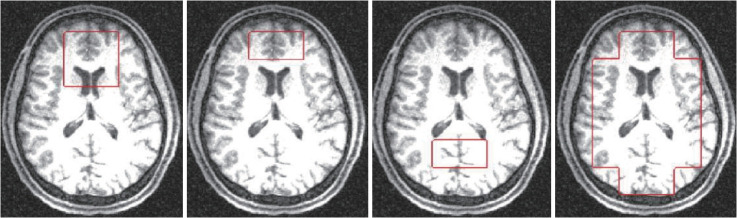

Methods: Twelve healthy controls (33.00±6.07 years) and 12 subjects diagnosed with SCZ or schizoaffective disorder (36.00±8.33 years) matched for age and sex, were recruited for this study. Hypoxic stress was induced during MR scans to elevate the energy demand on the subjects' bioenergetic systems. Participants breathed air with a lower oxygen concentration (FiO2=13%), maintaining their SpO2 levels (86%) during the initial phase of the scan. 31Phosphorus MR spectroscopy was employed to examine metabolite levels, including phosphocreatine (PCr), β-adenosine triphosphate (ATP), and inorganic phosphate (Pi), as well as the ratios of PCr/Pi and PCr/β-ATP, in regions such as the prefrontal cortex (PFC), anterior cingulate cortex (ACC), and posterior cortex (POC), as well as across the entire brain, during both hypoxia and hyperoxia scans.